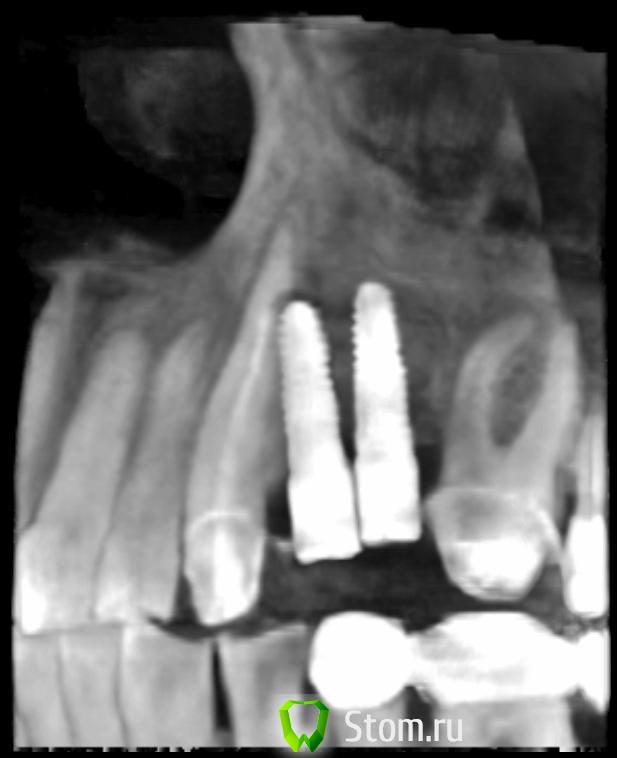

ern Опубликовано 15 апреля, 2012 Поделиться Опубликовано 15 апреля, 2012 Уважаемые господа, очень бы хотелось узнать ваше мнение по положению имплантов.Снимки сделаны через 6 месяцев, незначительно изменен ракурс.С уважением. Ссылка на комментарий

ern Опубликовано 16 апреля, 2012 Автор Поделиться Опубликовано 16 апреля, 2012 Добрый вечер! Спасибо за ответ. Меня интересует -насколько критичен контакт импланта с корнем 3 зуба-будут ли проблемы с протезированием из-за отклонения по осям и расстояния Диаметр 3,4 С уважением. Ссылка на комментарий

Sahan Опубликовано 16 апреля, 2012 Поделиться Опубликовано 16 апреля, 2012 Добрый вечер! -насколько критичен контакт импланта с корнем 3 зуба-будут ли проблемы с протезированием из-за отклонения по осям и расстояния Диаметр 3,4 С уважением.1) Время покажет, все зависит от наличия очага воспаления в этой области.2) Проблемы с протезирование будут и периимплантит будет. Ссылка на комментарий

Sahan Опубликовано 16 апреля, 2012 Поделиться Опубликовано 16 апреля, 2012 Да вы сами посмотрите на снимок. Имплантаты стоят слишком близко друг к другу плюс криво - отсюда и сложности. А решение только радикальное: удалить импл, костная пластика и повторная установка но уже в правильном положении и с соблюдением правила 1,5-3-1,5. Ссылка на комментарий